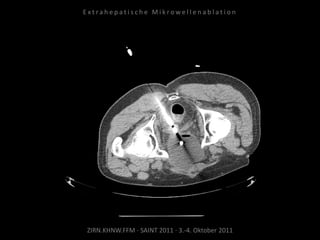

Metastase medial des linken

Musculus iliacus:

1 Nadelposition.